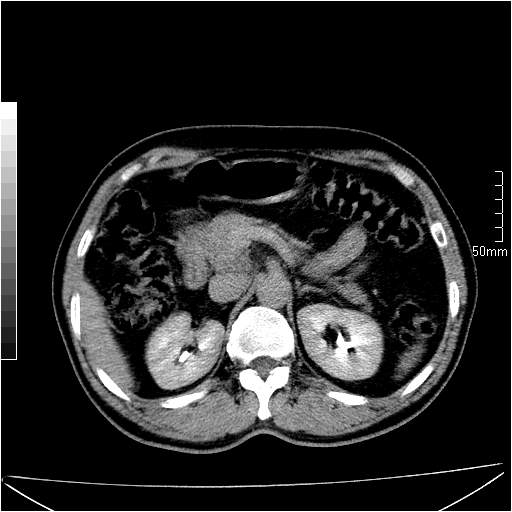

男性,54岁,皮肤黄染,搔痒一周余.b超示肝左叶回声异常.初步诊断1胆总管下段结石2胆囊结石伴慢性胆囊炎请各位战友帮忙看一下肝脏多发低密度如何解释恰当.增强效果不是很好.请大家见谅.

胆总管及肝内胆管扩张,考虑是结石!但,肝内的低密度区增强不明,可能是肝ca,因为肝ca在增强时呈快进快出.另年胆总管扩张原因,可以考虑一下是不是,胆管ca.再次要考虑肝内的低密度是否为海绵状血管瘤所致!

首先,胆总管下端结石梗阻伴肝内胆管扩张可确定。

其次,增强动脉期肝静脉显影,肝实质密度不均。——此为右心功能不全引起肝淤血的表现。

另外,肝八段低密度占位,呈多灶性,考虑肝脓肿或肝癌可能,(图像质量欠佳)建议进一步检查。

既然做了增强,为什么光提供延时期片子,肝动静脉期肝右叶前下段病灶增强如何?另外胆囊壁增厚,欠规整,内密度不均,与肝右叶病灶分界不清,增强表现怎样?肝内胆管轻度扩张,胆总管扩张,但未见明显结石影,也应提供增强早期图像才好鉴别扩张原因。片子较清,但不够完整,暂考虑1.胆囊癌肝局部浸润,或肝癌胆囊侵犯,2.胆总管下端或胰头钩突部占位。总之本人看不明白,请高手画图指示,先谢了!

由于胆囊窝内结构显示不清,肝脏病灶又邻近胆囊窝首先考虑胆囊癌肝受侵犯。而后因肝脏病灶强化有渐进改变,且相邻胆管扩张,故考虑肝胆管细胞癌待排。